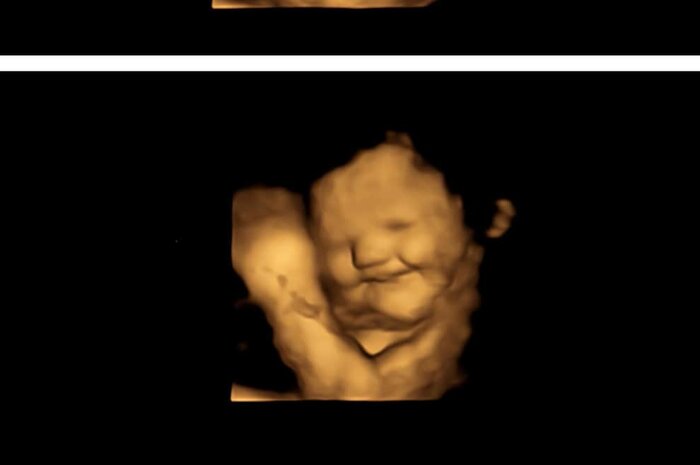

کارشناسانی از دانشگاه دورهام با تهیه و بررسی تصاویر سونوگرافی چهار بعدی از ۱۰۰ زن باردار، نوع واکنش جنینها را مورد بررسی قرار دادند.

این بررسی نشان داد که جنین برای مثال، نسبت به طعم هویج بیشتر با چهره خندان اما به طعم کلم با حالت ناراحتی و گریه واکنش نشان میدهد.